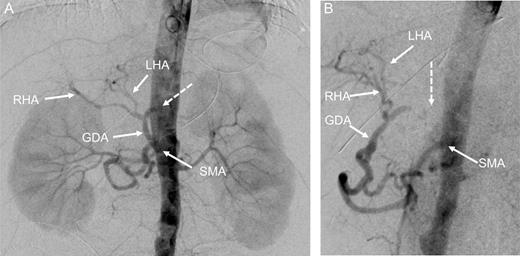

At this point, the patient was recommended for further investigation in the Interventional Radiological Department for both diagnosis confirmation and, most importantly, to provide an opportunity for stenting the celiac trunk. In order to accomplish this, gastro-duodenostomy, choledoco-choledocostomy (anastomosis between the resected common bile duct) and jejuno-jejunostomy re-anastomosis were performed, and a temporary abdominal closure was done. The patient was taken to the Radiological Department. CT and angiography (Figs 2 and 3) showed that there was a narrowing part of the celiac trunk, and distal to this part, there was an occlusion (high degree of stenosis) of the celiac artery. In addition, retrograde filling of the GDA could be appreciated through the patent SMA (Fig. 3). A stent was considered impossible due to the high degree of stenosis that was a nearly total occlusion of the celiac trunk.

Contrast-enhanced CT in the arterial phase: axial (A) and sagittal (B) maximum intensity projections (MIP), and coronal oblique 3D volume-rendered (VR) images (C) demonstrating proximal celiac artery narrowing (arrow) due to compression by the median arcuate ligament. Downstream, an additional high-degree stenosis of the celiac trunk can be appreciated (dashed arrow).

Digital subtraction angiography (DSA) with pigtail catheter placed in the abdominal aorta: coronal (A) and 70° left anterior oblique (LAO) projections (B) demonstrating complete occlusion of the celiac trunk (dashed arrow). In addition, retrograde filling of the GDA can be appreciated through the patent SMA. RHA, right hepatic artery; LHA, left artery.